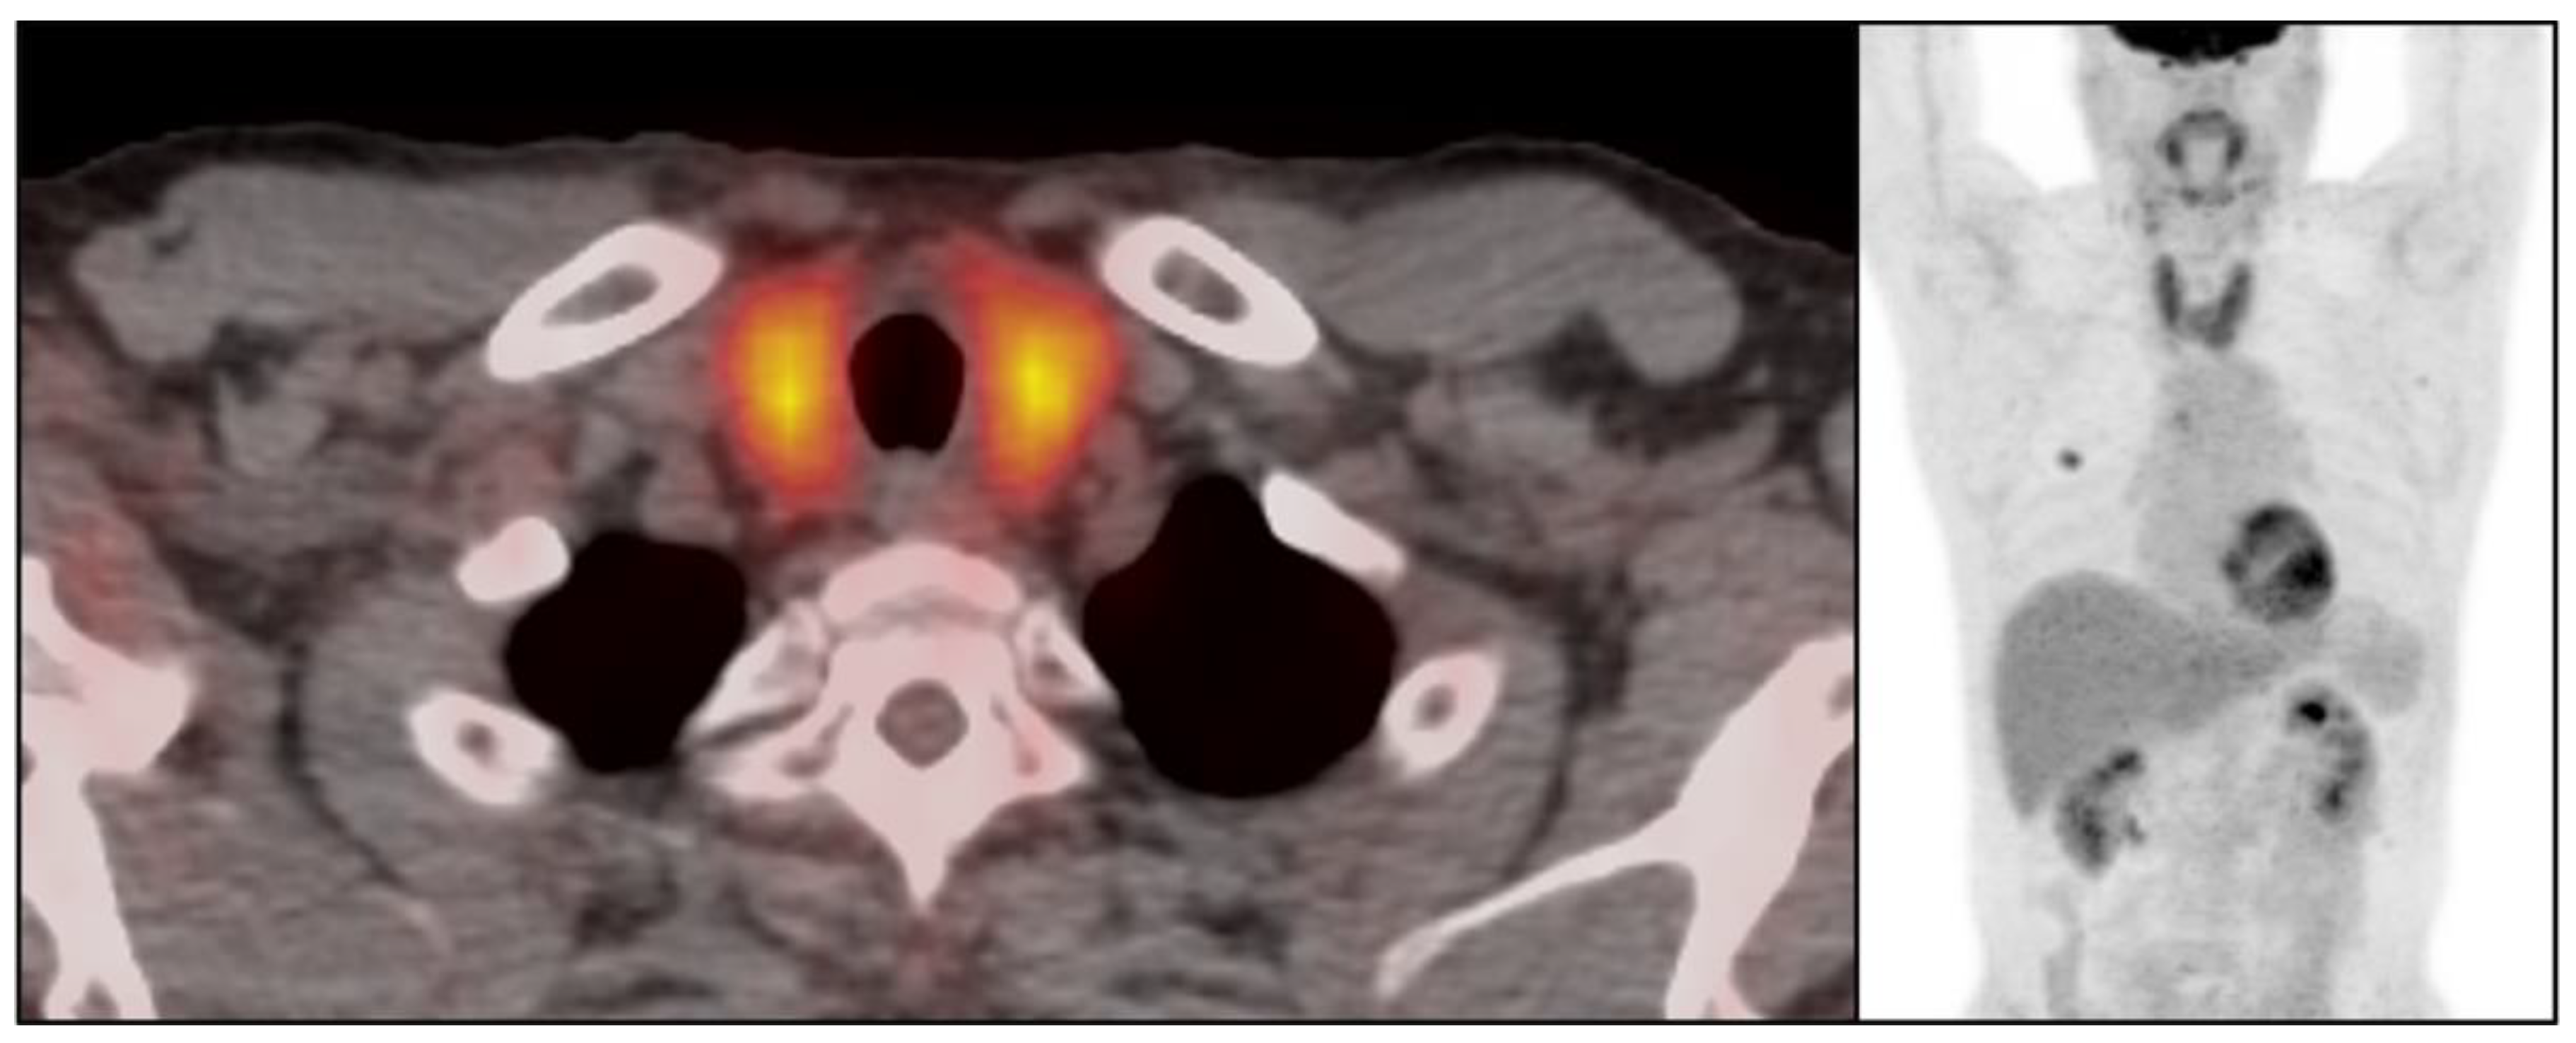

There were 50 patients (50/534, 9.4%) who showed imaging findings indicative of thyroiditis during ICI therapy (Figure 1). The median time from the initiation of therapy to the first CT scan with positive imaging findings was 9.5 weeks (range: 0.9–87.4 weeks). The most common CT finding for thyroiditis was diffuse hypodense attenuation of the thyroid gland, which was seen in 36 patients (36/50, 72%); 15 of these patients also demonstrated enlargement of the thyroid gland and 12 patients demonstrated atrophy (Figure 1). The heterogeneous attenuation of the gland was noted in 12 patients (12/50, 24%), with accompanying enlargement in 7 patients and atrophy in 1 patient (Figure 2). Among the 12 patients with heterogeneous enlargement, 3 patients also had a diffuse increased FDG uptake on PET/CT. Two patients (2/50, 4%) did not show any morphologic changes with the CT scan but had a diffuse increased FDG uptake of the thyroid gland on PET/CT (Figure 3). There were no significant differences in the demographic and clinical parameters between patients with and without findings suggestive of thyroiditis (Table 1)

Figure 3.

Imaging findings of immune-related thyroiditis on FDG-PET/CT. 57-year-old woman with advanced lung cancer treated with nivolumab monotherapy. After 7.9 weeks of therapy, there was a diffuse FDG uptake of thyroid gland representing immune-related thyroiditis.

Imaging findings of immune-related thyroiditis have been described in previous studies, mainly focusing on the sonographic or PET/CT findings. On ultrasounds, the gland shows mild enlargement with diffuse low echogenicity [18], which is similar to other thyroiditis such as Hashimoto thyroiditis. The main difference between immune-related thyroiditis and Hashimoto thyroiditis is that the gland eventually becomes atrophic in immune-related thyroiditis, whereas Hashimoto thyroiditis remains enlarged mainly with diffuse fibrotic change [19]. On PET/CT, there is transient diffuse FDG uptake of the thyroid gland reflecting active inflammation [11,20]. A positive PET/CT finding is often present before the development of clinically overt thyroiditis, which can be used as a predictive indicator [20]. This study also reported the incidence of PET-positive thyroiditis as 22%, and there was a transient increase in FDG uptake with an SUVmax of 116% (IQR: 84–177; range: 52–300); additionally, a follow-up study found a resolution of FDG uptake with a median of 32 days (IQR: 79–194; range: 49–1045) [20]. In our study, there were five patients who had positive PET/CT findings among the forty-five patients who had PET/CT during ICI, whereby three of them showed both morphologic changes and increased metabolic activity and two of them showed FDG uptake of the gland without morphologic change. The evaluation of incidence or temporal changes in positive FDG-PET/CT among the study cohort was limited, as PET/CT is not routinely performed during follow ups on lung cancer.